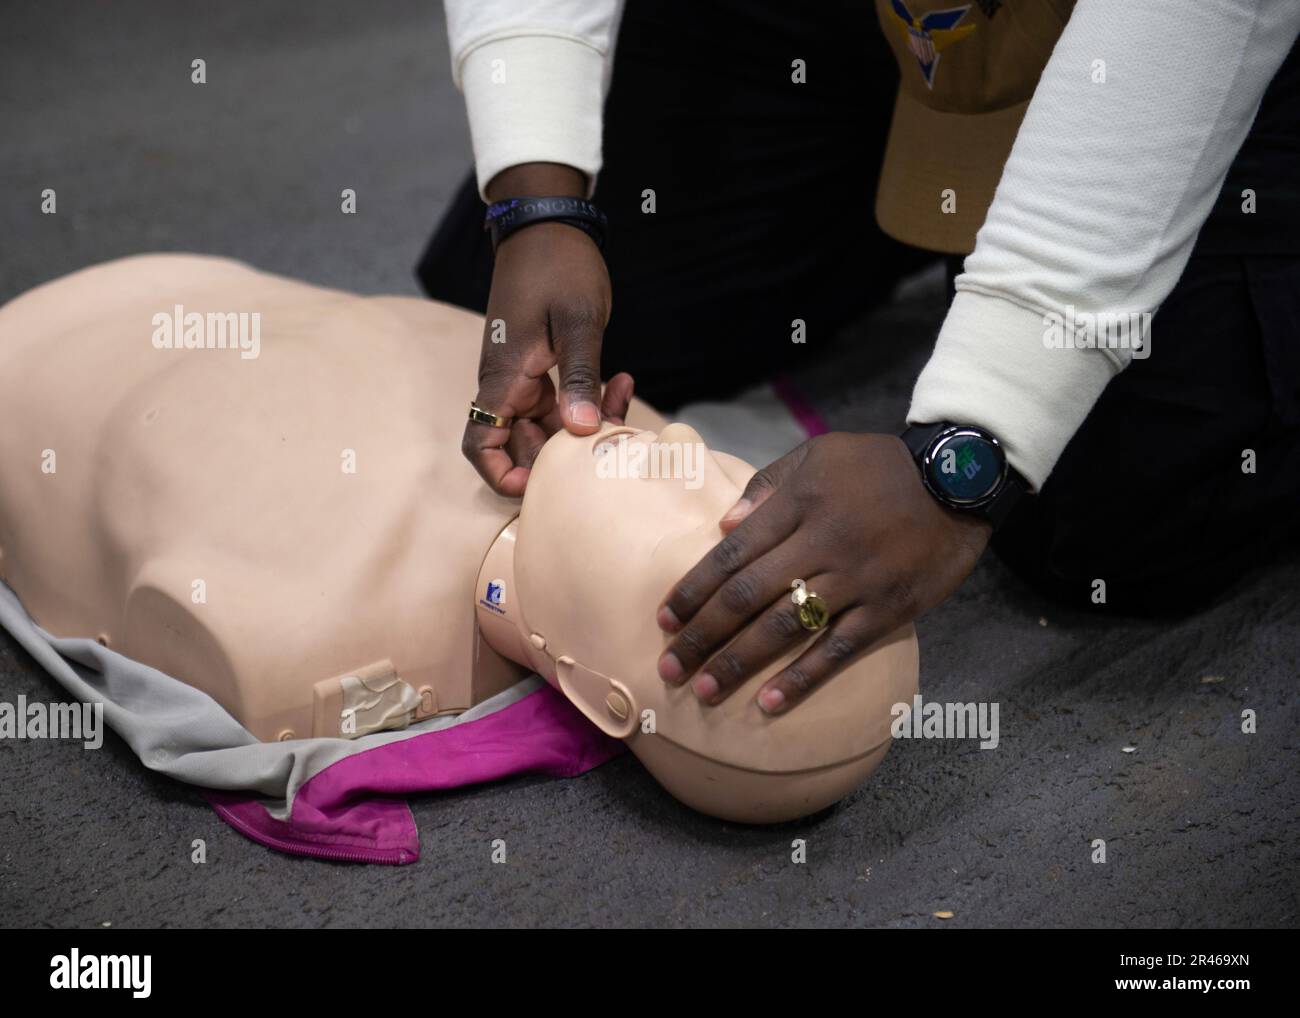

230118-N-MD461-1043 PACIFIC OCEAN (Jan. 18, 2022) Hospital Corpsman 3rd Class Ahmi Atsina, a native of New Orleans, La., instructs Sailors how to check for airway obstruction during CPR training in the jet shop aboard Nimitz-class aircraft carrier USS Carl Vinson (CVN 70). Vinson is currently underway conducting routine maritime operations. Stock Photohttps://www.alamy.com/image-license-details/?v=1https://www.alamy.com/230118-n-md461-1043-pacific-ocean-jan-18-2022-hospital-corpsman-3rd-class-ahmi-atsina-a-native-of-new-orleans-la-instructs-sailors-how-to-check-for-airway-obstruction-during-cpr-training-in-the-jet-shop-aboard-nimitz-class-aircraft-carrier-uss-carl-vinson-cvn-70-vinson-is-currently-underway-conducting-routine-maritime-operations-image553329917.html

230118-N-MD461-1043 PACIFIC OCEAN (Jan. 18, 2022) Hospital Corpsman 3rd Class Ahmi Atsina, a native of New Orleans, La., instructs Sailors how to check for airway obstruction during CPR training in the jet shop aboard Nimitz-class aircraft carrier USS Carl Vinson (CVN 70). Vinson is currently underway conducting routine maritime operations. Stock Photohttps://www.alamy.com/image-license-details/?v=1https://www.alamy.com/230118-n-md461-1043-pacific-ocean-jan-18-2022-hospital-corpsman-3rd-class-ahmi-atsina-a-native-of-new-orleans-la-instructs-sailors-how-to-check-for-airway-obstruction-during-cpr-training-in-the-jet-shop-aboard-nimitz-class-aircraft-carrier-uss-carl-vinson-cvn-70-vinson-is-currently-underway-conducting-routine-maritime-operations-image553329917.htmlRM2R469XN–230118-N-MD461-1043 PACIFIC OCEAN (Jan. 18, 2022) Hospital Corpsman 3rd Class Ahmi Atsina, a native of New Orleans, La., instructs Sailors how to check for airway obstruction during CPR training in the jet shop aboard Nimitz-class aircraft carrier USS Carl Vinson (CVN 70). Vinson is currently underway conducting routine maritime operations.